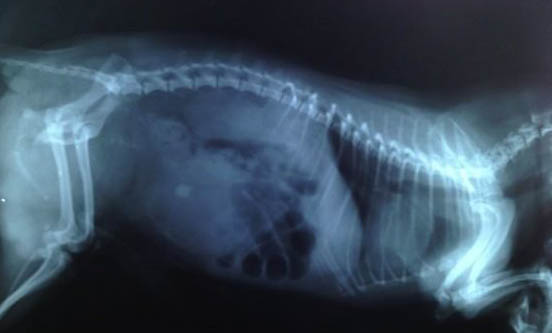

公犬绝育后怎么护理啊

公犬绝育后,要注意给它做好以下护理:1、在狗狗做完绝育手术结束两个小时后才能给狗狗饮水、五个小时后再让狗狗进食,避免狗狗出现呕吐或造成气管堵塞等情况;

2、狗狗绝育留下的伤口一般需要一个星期左右的时间才能恢复,在这期间注意每天24小时给狗狗佩戴项圈,防止狗狗舔舐伤口,尽量保持其伤口干燥,避免其伤口发生感染;

3、在狗狗伤口恢复期间,避免狗狗进行剧烈运动,让它多休息,每天带它出门散散步即可;

4、注意观察狗狗的伤口是否有发炎感染的情况,如果有,及时带狗狗去宠物医院处理。